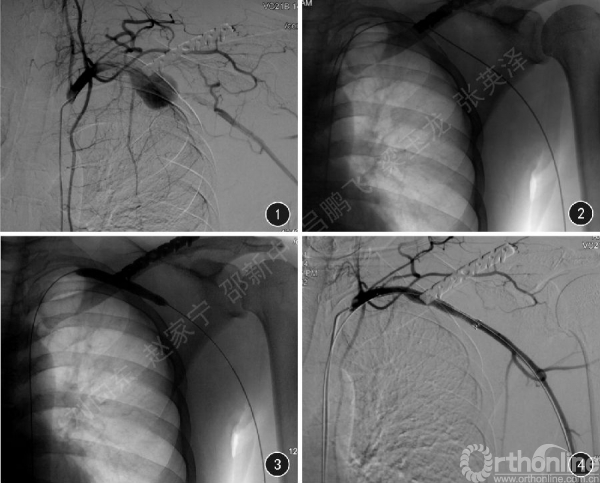

患者男,29岁。因“左锁骨骨折术后左上肢麻木、活动受限5d”,于2014年9月10日入住我院手外科。患者2014年9月5日不慎摔伤左上肢,当即肿胀疼痛,于当地医院行“左锁骨骨折内固定术冶,术后出现左上肢麻木、活动受限、间断性左后背痛5 d。查体:左上肢诸肌肌力芋级,未见明显萎缩;左肘关节及腕关节主动屈伸活动受限;左手“爪形手冶畸形,鱼际肌及内在肌萎缩,小鱼际区皮肤及环指尺侧和小指皮肤干燥、感觉迟钝;2~5 指内收外展活动受限,环小指末节屈曲力弱;左尺、桡动脉搏动减弱,左手皮温稍低。患者入院时提供的当地医院检查资料如下:(1)左锁骨正位X 线片,提示左锁骨中段骨折术后、断端复位欠佳;(2)左上肢动脉彩超,提示左上肢动脉血流频谱异常、血流速度低;(3)左上肢动脉造影片,提示左锁骨下动脉远端假性动脉瘤合并局部动脉闭塞。患者批入院后于2014 年9 月15 日在全身麻醉下行左锁骨下血管、臂丛神经探查修复加锁骨骨折内固定术。术中可见:左锁骨至胸小肌后方腋动脉处局部膨大,可触及搏动,表面光滑菲薄,与臂丛神经束支部粘连,远端动脉未触及搏动。考虑假性动脉瘤形成致局部动脉闭塞,拟行动脉瘤切除+血管重建术。但术中发现瘤体与周围组织粘连严重,分离暴露血管困难;为免发生假性动脉瘤破裂大出血,术中请血管外科医师急会诊并协助手术,同时与患者家属沟通后决定改行择期血管腔内隔绝术,故对左锁骨下动脉假性动脉瘤暂未作处理,复位锁骨骨折。患者于2014 年9 月23 日局部麻醉下行左锁骨下动脉闭塞开通术+ 左锁骨下动脉假性动脉瘤腔内隔绝术。术中动脉造影可见左锁骨下动脉远端假性动脉瘤致局部动脉闭塞(图1)。顺行开通闭塞段时由于导丝反复进入假性动脉瘤瘤体内,未能通过闭塞段;为避免导丝刺破假性动脉瘤,在超声引导下经左桡动脉鞘逆行穿入导丝,成功通过左锁骨下动脉闭塞段及假性动脉瘤建立通路(图2)。利用导丝通路将5F 右股动脉导管鞘置换为10F 动脉鞘,沿导丝置入8 mm x 60 mm 血管成形术球囊扩张导管(Bard Rival)对左锁骨下动脉狭窄段扩张(图3)。撤出球囊导管,沿导丝置入10 mm x 80 mm 血管覆膜支架(Fcmluency Plus Bard),根据造影结果及骨性标记将支架释放覆盖假性动脉瘤,再行造影可见支架位置适当,假性动脉瘤未见显影,左锁骨下动脉、腋动脉、肱动脉血流通畅(图4)。右股动脉10F 动脉鞘拔出后用2 把6F 血管缝合器(Perclose ProGlide Abbott )缝合右股动脉穿刺部位。术后第5 天复查:左上肢麻木、左上肢活动受限有缓解(左上肢抬高>90°~<120°),左背部疼痛消失,左手2~5 指伸展幅度增大,但仍不能完全伸展,左侧尺、桡动脉搏动明显增强。术后4 个月随访,患者左上肢麻木、左上肢活动受限缓解(左上肢抬高> 120°~<180°),左手不能完全伸展,左尺、桡动脉搏动正常。

图1 DSA 像显示囊袋状假性动脉瘤,瘘口位于左锁骨下动脉远端(第1 肋骨与锁骨交汇处)

图2 数字摄影图像显示从左桡动脉鞘逆行穿入的导丝顺利通过左锁骨下动脉假性动脉瘤狭窄段,成功建立导丝通路

图3 数字摄影图像显示PTA 球囊导管经导丝通路对狭窄段扩张

图4 DSA 像显示覆膜支架经导丝通路释放后成功对假性动脉瘤进行了隔绝,未见造影剂外溢,血流通畅